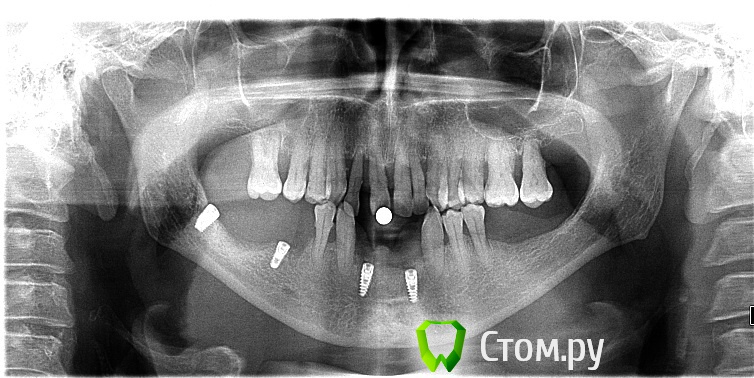

samanta66 Опубликовано 12 октября, 2014 Поделиться Опубликовано 12 октября, 2014 Уважаемые доктора, нужна консультационная помощь.3 месяца назад поставлены импланты на месте 32 и 42, 36 и 38 зубов (если не ошибаюсь с нумерацией), скоро протезирование. Сохраняется чувство легкого онемения части подбородка. Периодически (особенно при и сразу после жевания) чувствую стискивание зубов (33 и 34), онемение или "мурашки", покалывание в правой части губы. Затем указанные симптомы проходят, но периодически (несколько раз в день) появляются снова. По ощущениям их интенсивность всё-таки уменьшилась со временем.1. Каковы перспективы? Можно ли надеяться на полное восстановление чувствительности. Не будет ли проблем при протезировании (установлении абатмента и коронок)?2. Оцените качество установления имплантов? ОПТГ приложила. Спасибо. Ссылка на комментарий

SergioS Опубликовано 12 октября, 2014 Поделиться Опубликовано 12 октября, 2014 (изменено) Интенсивный выбор позиции имплантов справа. Сходите на консультацию к другому доктору и сделайте кт. Чем раньше тем лучше. Изменено 12 октября, 2014 пользователем SergioS Ссылка на комментарий

faity Опубликовано 12 октября, 2014 Поделиться Опубликовано 12 октября, 2014 компрессия НЧК имплантом возможна, +1 к КТ. чем раньше тем лучше Ссылка на комментарий

samanta66 Опубликовано 13 октября, 2014 Автор Поделиться Опубликовано 13 октября, 2014 КТ сделала, прилагаю.Пожалуйста, прокомментируйте. Ссылка на комментарий

faity Опубликовано 13 октября, 2014 Поделиться Опубликовано 13 октября, 2014 впритирку имплант стоит, я бы выкрутил Ссылка на комментарий